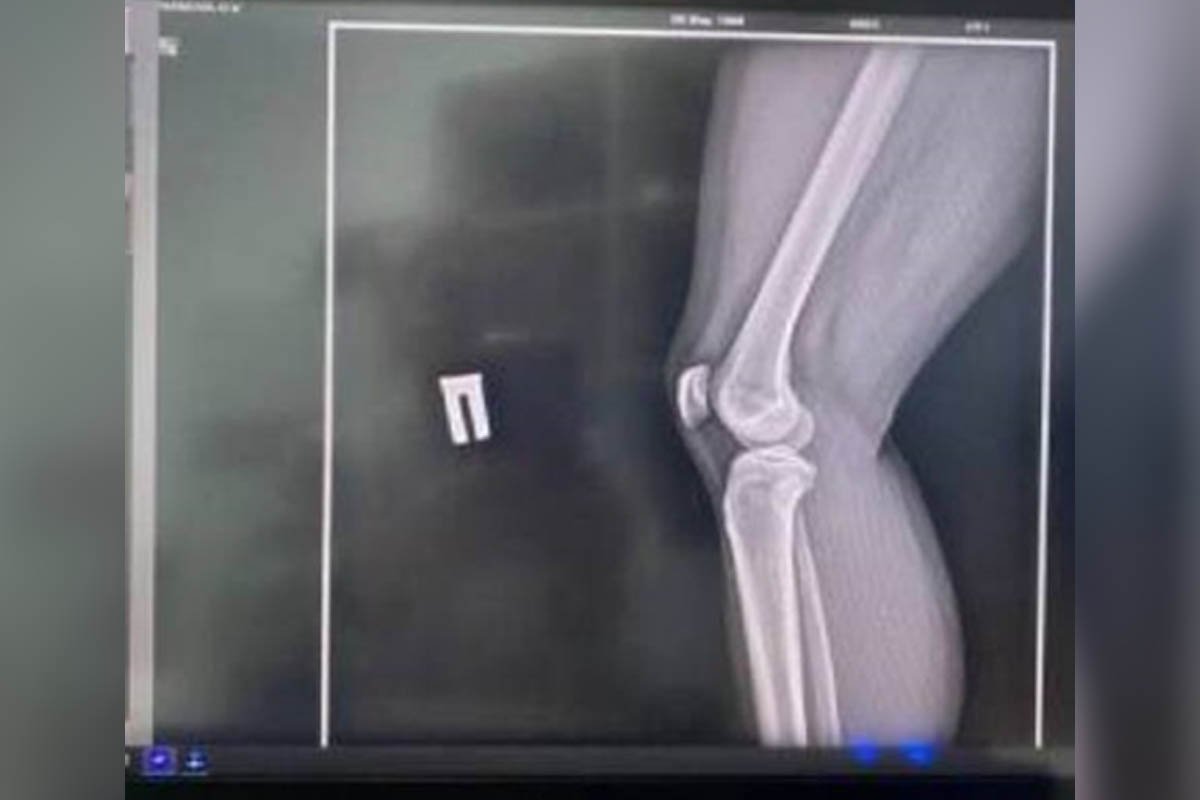

“Я захищалася і ударила йому в обличчя. Він дуже розлютився і вдавив мене в землю (не знаю як інакше описати) просто вдавив. Оскільки я стояла і не встигла згрупуватися, одразу відчула, що нога не так пішла і щось з коліном”, - згадує учасниця конфлікту.